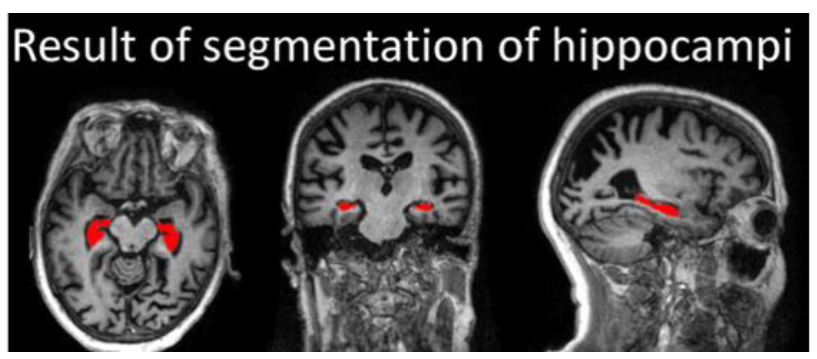

CT、MRIによる形態画像診断では、脳の萎縮、脳梗塞・脳出血、脳腫瘍、水頭症、慢性硬膜下血腫などの有無を調べます。 アルツハイマー型認知症では、脳の全般的萎縮と海馬(矢印部分)の萎縮(脳溝拡大、脳室拡大、側脳室下角拡大など)が著明である。 連載第11回で示したものは水平断で、ここでは冠状断を示した 本書で紹介している治療法等は、著者が臨床例. 近畿大学病院放射線診断科で認知症に対する画像検査を受けられた患者様・ご家族の皆様・・・ お知らせ 近畿大学病院放射線診断科(以下、当科)では、「認知症患者の診療情報を用いた認知症患者データベースの構築」という臨床研究を行っています。. 認知症ドッグで軽度認知症を早期発見して適切な対策を行うことにより、症状の進行を阻止することが可能となり、認知症の症状が最後まで出ずにすむケースもあります。 検査内容 1心理学的検査(認知力・記憶力) 2mri検査.

海馬のmri脳画像診断